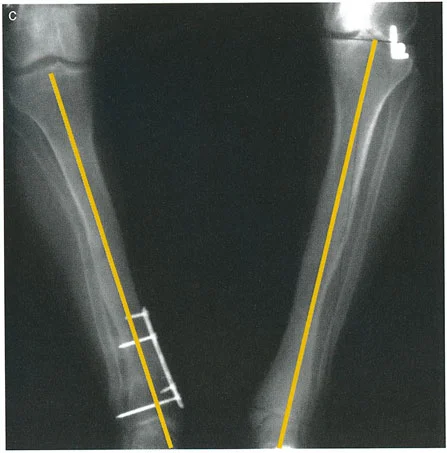

* الأشعة السينية (X-rays) الواقفة لكامل الطرف السفلي: هذه الأشعة ضرورية لتقييم المحاذاة الكلية للطرف السفلي تحت تأثير وزن الجسم. يطلب الأستاذ الدكتور محمد هطيف صورًا شعاعية كاملة الطول للساق أثناء الوقوف (Full-length standing alignment films) لتقييم المحور الميكانيكي للساق وتحديد زوايا المفاصل بدقة.

* رسم المحاور الميكانيكية والتشريحية: لتحديد نقطة مركز دوران التشوه (CORA)، وهي النقطة التي يجب أن تتم عندها الجراحة لتصحيح التشوه بأقل قدر من المضاعفات.